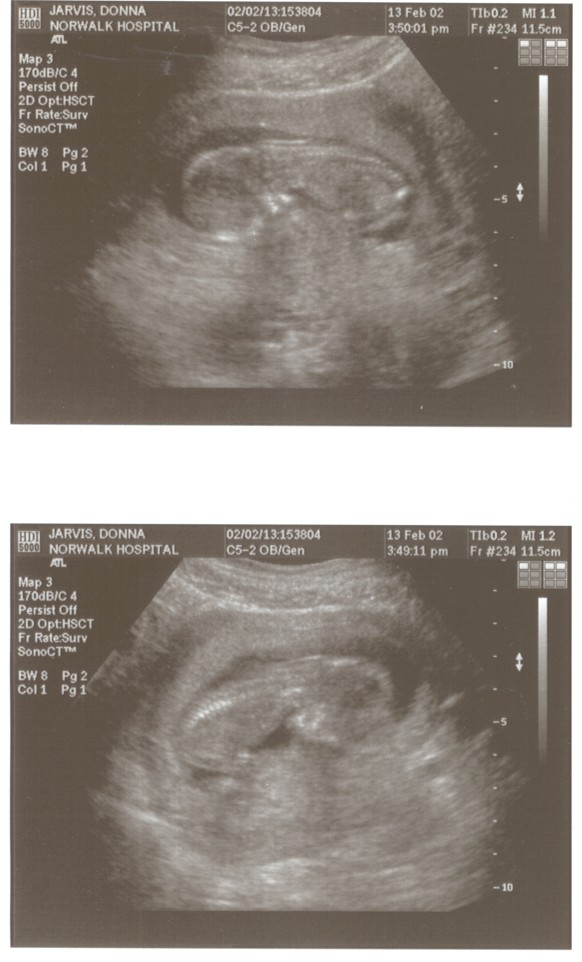

6/15/02 (Week 32)- We had our last ultrasound this week. The baby appears in good health and is estimated at 3 pounds, 14 ounces which is around the median size. We saw her lips and her tongue and watched her yawn. We also saw her little heart beating and watched her kick. Mom, however, is getting more and more uncomfortable - back aches, feet hurt, hands, feet and legs swollen. And she gained a little too much weight this visit, so we are now watching what we eat. We picked out our baby announcements this week and the room will finally be painted next week, so we are making some progress on getting everything done before the baby arrives!